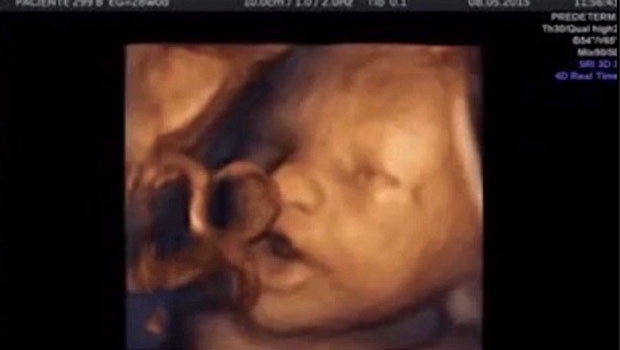

Fetüslerin kulaklarının hamileliğin 14. Haftasında tamamen geliştiğini hali hazırda bildiklerini ancak bir fetüsün duyma yetisini en erken 18 haftada kazandığını düşündüklerini belirten uzmanlar, bu deneyde 16 haftalık fetüslerin çalınan müziğe doğrudan tepki verdiğini gözlemlediklerini söyledi.

Uzmanlar, fetüslerin annelerinin vücudunun içinde çalınan Johann Sebastian Bach’a ait klasik müzik parçasını duyduklarını ağız ve dudaklarını sanki konuşmak ya da şarkı söylemek istiyormuşçasına hareket ettirdiğini söyledi.